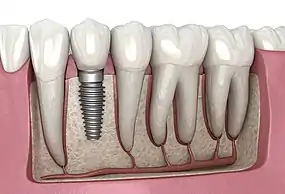

Dental Implant, 3D Illustration

A dental implant (also known as an endosseous implant or fixture) is a prosthesis that interfaces with the bone of the jaw or skull to support a dental prosthesis such as a crown, bridge, denture, or facial prosthesis or to act as an orthodontic anchor. The basis for modern dental implants is a biological process called osseointegration, in which materials such as titanium or zirconia form an intimate bond to the bone. The implant fixture is first placed so that it is likely to osseointegrate, then a dental prosthetic is added. A variable amount of healing time is required for osseointegration before either the dental prosthetic (a tooth, bridge, or denture) is attached to the implant or an abutment is placed which will hold a dental prosthetic/crown.